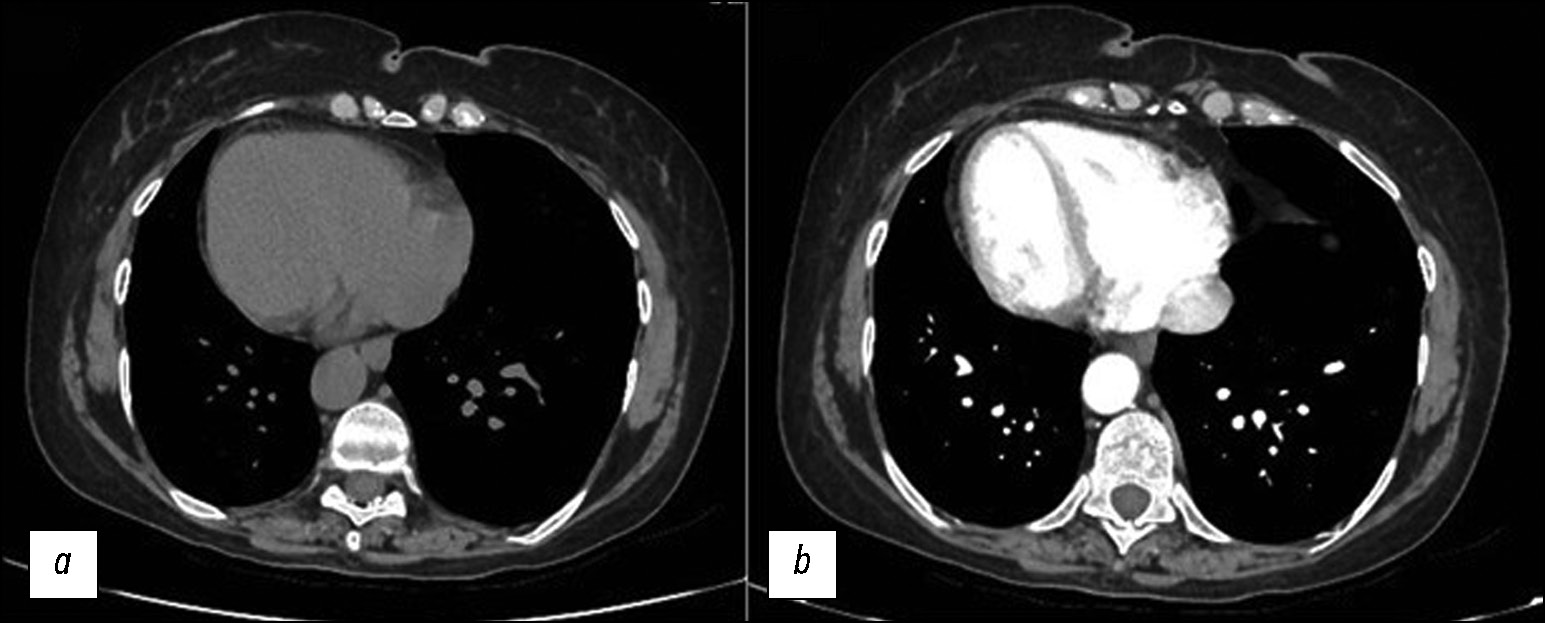

Атрезия лёгочных вен — редкий порок развития, который может возникать как изолированно, так и в сочетании с другими врождёнными пороками развития сердечно-сосудистой системы, например, с таким как гипоплазия лёгочной артерии. Атрезия лёгочных вен приводит к изменениям в работе сердечно-сосудистой системы. Данный порок развития чаще диагностируется в младенческом и раннем детском возрастем ввиду рецидивирующих эпизодов пневмонии и кровохарканья. Во взрослом возрасте атрезия лёгочных вен встречается намного реже, клинически характеризуется такими проявлениями, как одышка при физической нагрузке и кровохарканье. Однако в редких случаях клинические симптомы отсутствуют, при этом изменения в паренхиме лёгких носят неспецифический характер, ввиду чего могут быть ошибочно расценены как проявления различных лёгочных заболеваний в том числе воспалительного генеза. В представленной статье описано клиническое наблюдение сочетания односторонней атрезии лёгочных вен с гипоплазией лёгочной артерии и интерстициальными изменениями в гипоплазированном лёгком у молодого мужчины без жалоб со стороны органов дыхания. Патологии впервые выявлены в 21 год по данным компьютерной томографии с контрастным усилением.

361-369